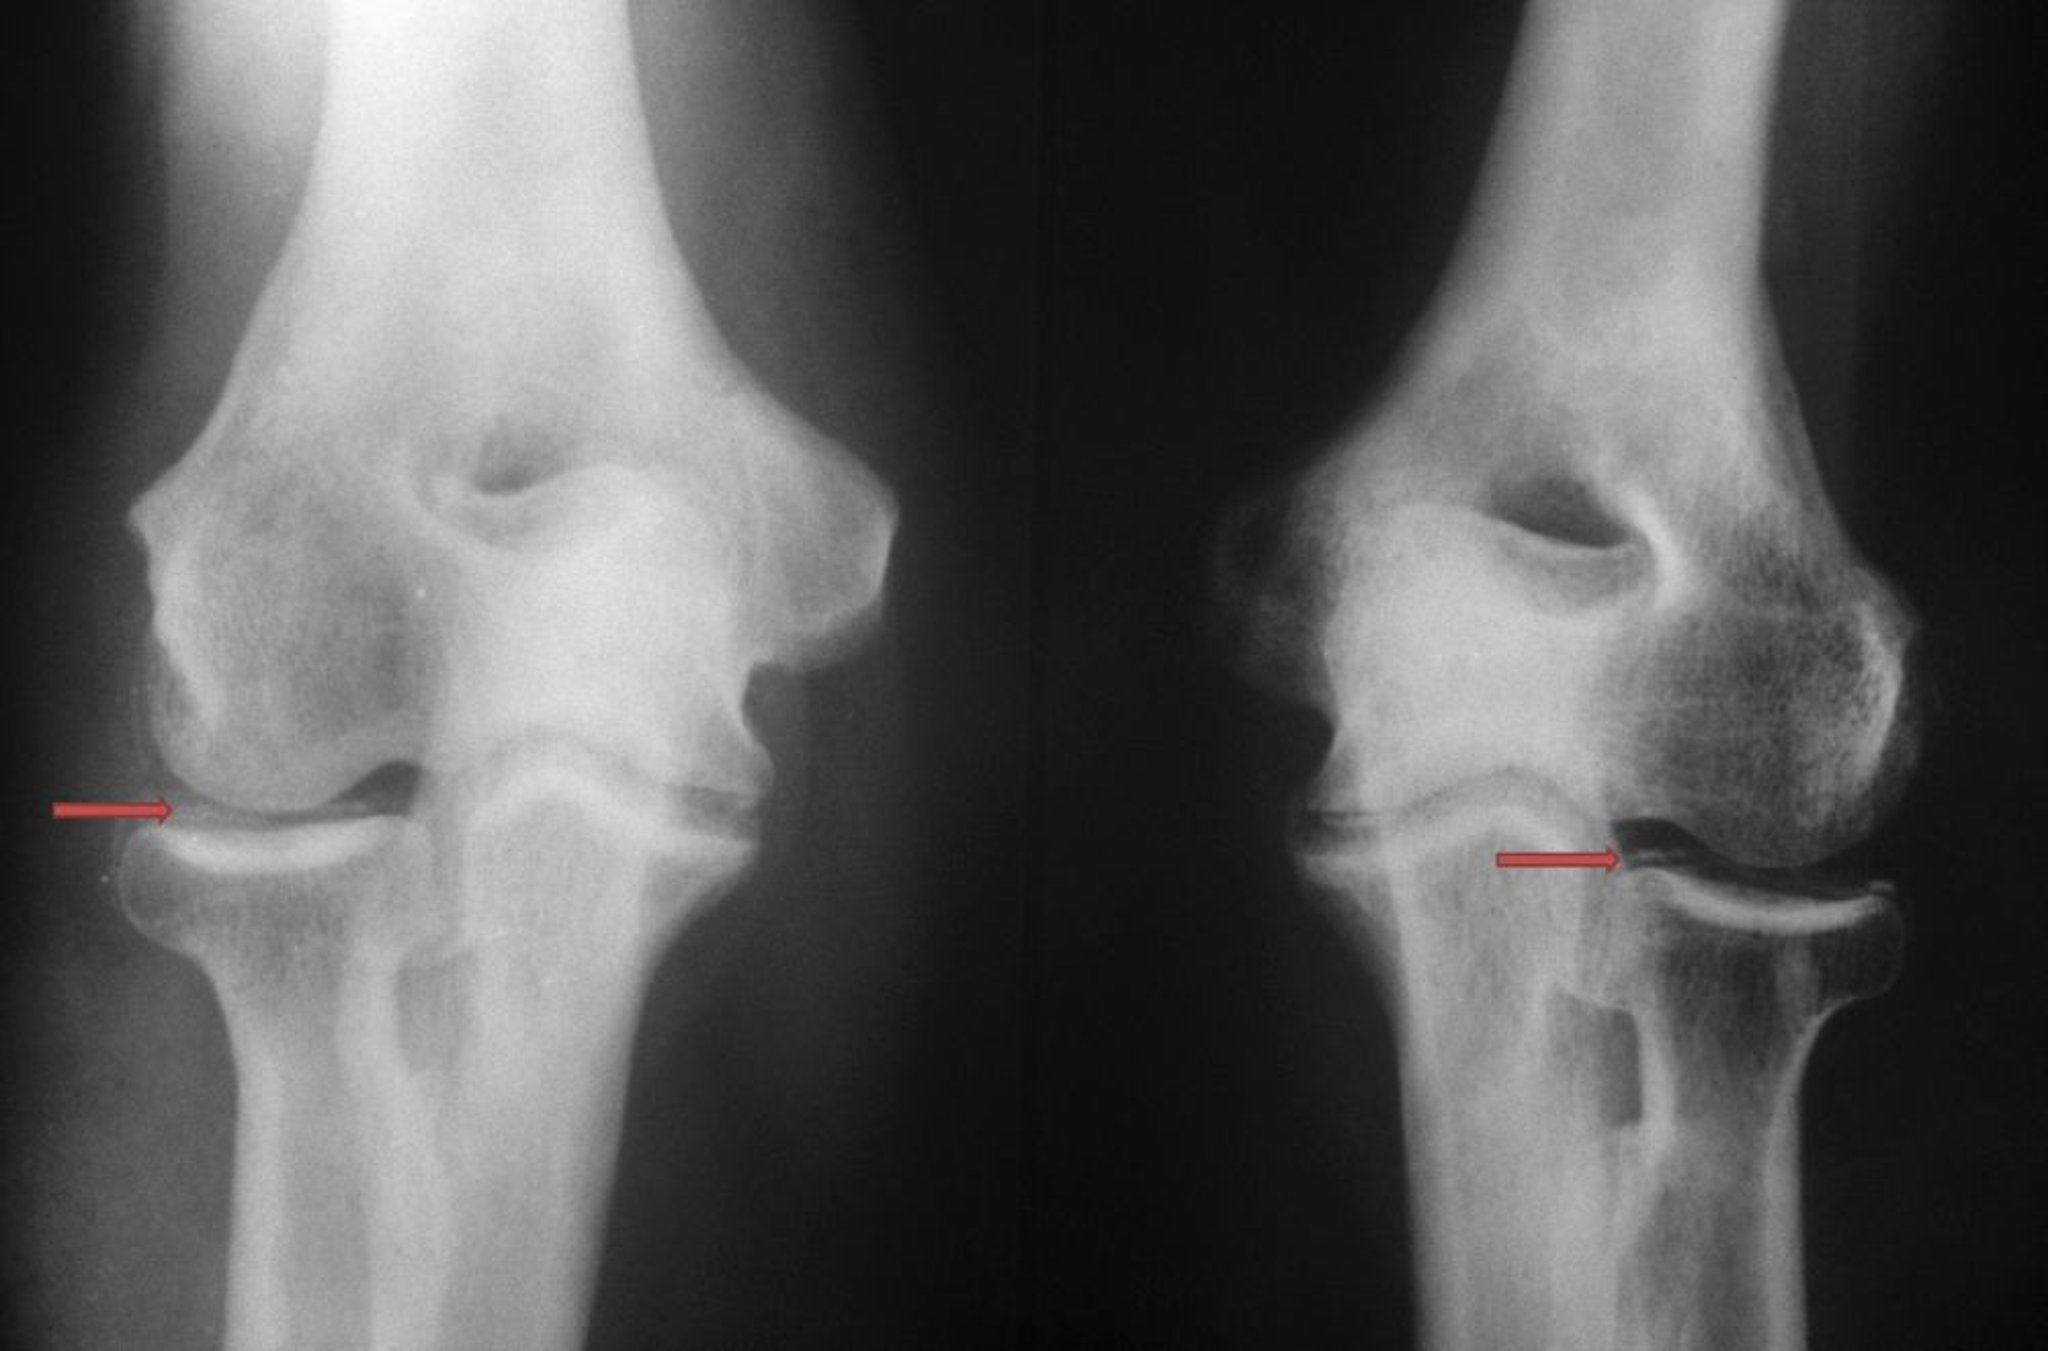

Artrite da pirofosfato di calcio (malattia da deposito di cristalli di pirofosfato di calcio diidrato, artropatia da pirofosfato o pseudogotta)

La deposizione di cristallo di calcio diidrato di pirofosfato è visibile con radiopacità mal definite e di densità variabile (frecce rosse) all'interno dell'articolazione del gomito.